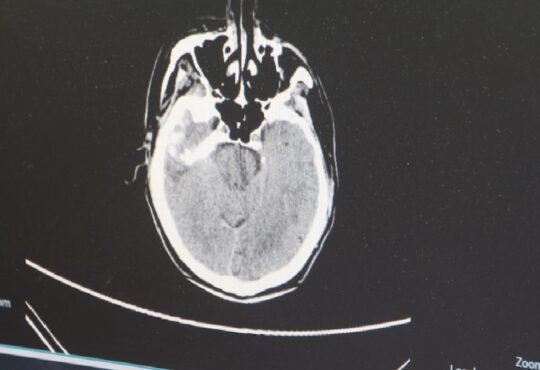

Genellikle başka şikayetler ile başka branşlara başvurmuş hastalarda yapılan Tüm Batın Ultrasonografi si, Batın BT (Bilgisyarlı Tomografi) ya da Batın MR ile tanı konur.